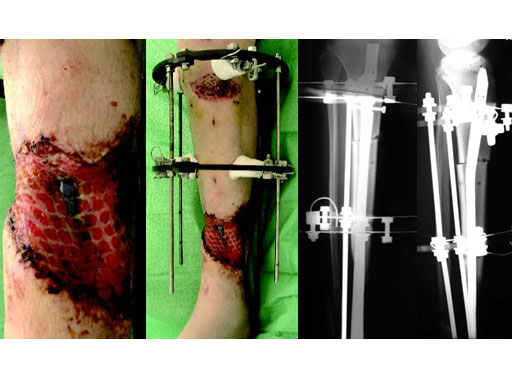

A 33-year-old female sustained a grade III open fracture of the right lower leg.

Case provided by Michael Raschke, Mnster, DE